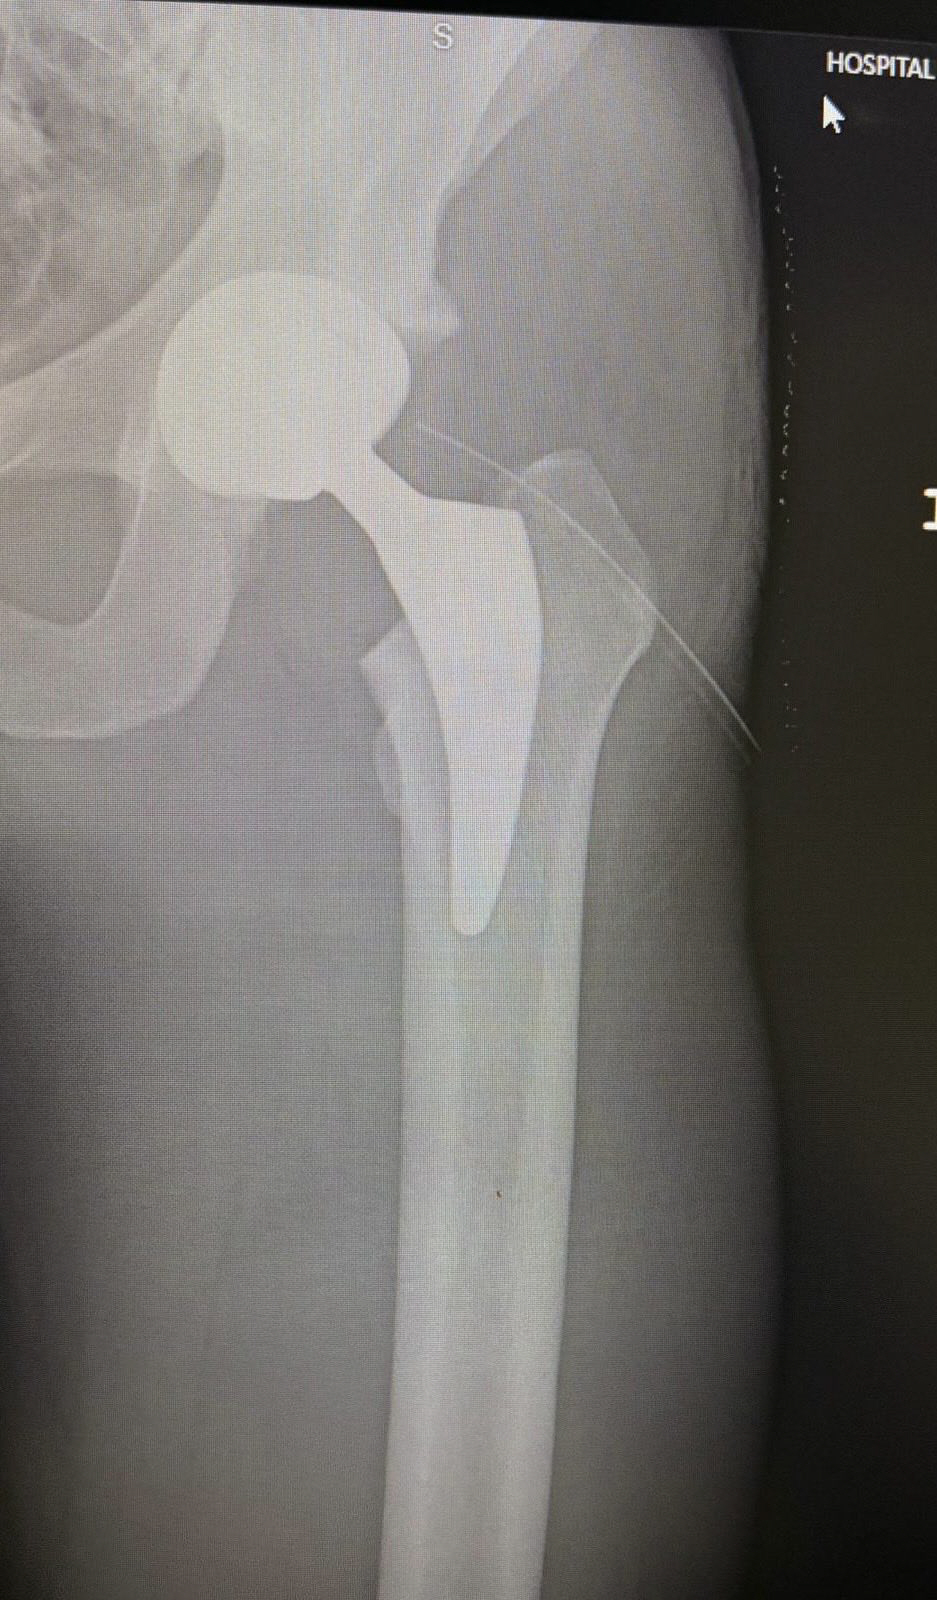

라멜라는 29일(한국시각) 자신의 SNS를 통해 '인공 고관절 치환 수술' 근황을 직접 전했다. 병원에서 찍은 사진들과 엑스레이 스캔 사진, 수술 모습이 담긴 짧은 영상을 공개한 후 '조금 아프긴 하지만 새로운 고관절을 갖게 됐다. 이 인공관절이 고통 없는 삶의 시작이 되길 바란다'고 썼다. '모두에게 안부를 전하며 항상 응원 메시지를 보내주시는 모든 분들께 감사드린다'고 덧붙였다.

지난해 라멜라는 'TyC 스포츠'와의 인터뷰에서 자신의 고관절 문제를 솔직하게 털어놓은 바 있다. 당시 그는 "오랫동안 나를 괴롭혀온 신체적인 문제 때문에 은퇴했다"면서 "이 문제에도 불구하고 가능한 한 축구를 즐기며 최선의 방식으로 커리어를 마무리하고 싶었지만, 상황이 꽤 어려웠다. 연골 마모와 퇴행성 관절염이 진행돼 문제가 더욱 심각했다"며 은퇴의 이유를 설명했다.

"지난 몇 년은 고관절 상태가 점점 더 악화돼 예전처럼 훈련할 수 없을 정도로 심각했기 때문에 훈련 방식을 바꿀 수밖에 없었다. 내 고관절이 평일 동안 특정 성능 수준을 유지할 수 없었기 때문"이라고 했다.